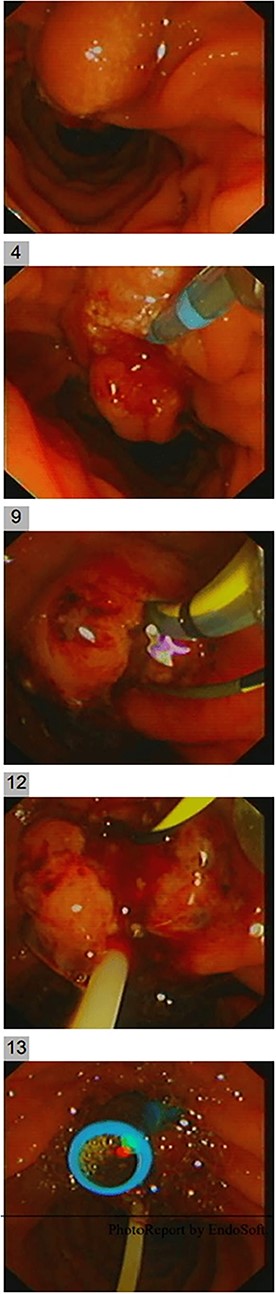

Endoscopic ultrasound (EUS) was carried out to delineate the anatomy and the location of the ampulla of vater (AOV) and showed an abnormally located AOV in the distal duodenum (D4) with dilated CBD. Endoscopic retrograde cholangiopancreatography [ERCP] was performed in the same setting with difficulties in cannulating the ectopic AOV that was associated with mucosal abnormality. After multiple trials, the cannulated pancreaticogram was unremarkable (Fig. 2). The double-wire technique is used to cannulate CBD. Cholangiogram revealed a short distal filling defect suspicious for stones. Several balloon sweeps were done, but no stones were retrieved. Cytology brushing and fluoroscopically guided intraductal biopsy were done. Also, mucosal ampullary biopsies were taken as well. Then, a CBD stent was inserted. The cytology was inconclusive. However, the ampullary biopsy revealed high-grade dysplasia, and invasive carcinoma could not be excluded. Therefore, she was suspected to have ampullary malignancy.

She had a CT chest to complete the staging workup, which was negative for metastasis. Eventually, she had a pancreaticoduodenectomy (Whipple procedure) with smooth postoperative recovery. The patient was discharged home on postoperative Day 7. The final histopathology came as moderately differentiated adenocarcinoma, pancreaticobiliary type with focal squamous differentiation (5%), invasion into the muscularis propria of the duodenum, and positive lymphovascular invasion with 1/12 LN positive for tumor deposits (Figs 3–6). All surgical margins were tumor-free. After a multidisciplinary meeting, the decision was made with proceed for adjuvant chemotherapy. Currently, she is on adjuvant chemotherapy, which she is tolerating well. Follow-up CT CAP at 3- and 6-month intervals postoperatively showed no evidence of recurrence or distant metastasis.